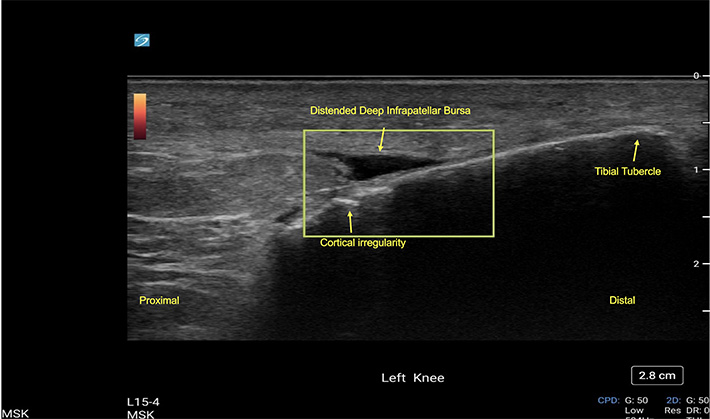

Long axis labeled view of the deep infrapatellar bursa with doppler overlay. Cortical irregularities are present. No hyperemia is visualized in the image. These findings represent a deep infrapatellar bursa fluid collection indicating possible bursopathy.